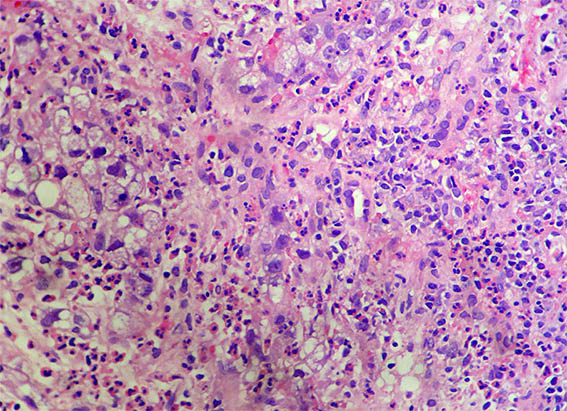

Figura 3.

H&E, X100.